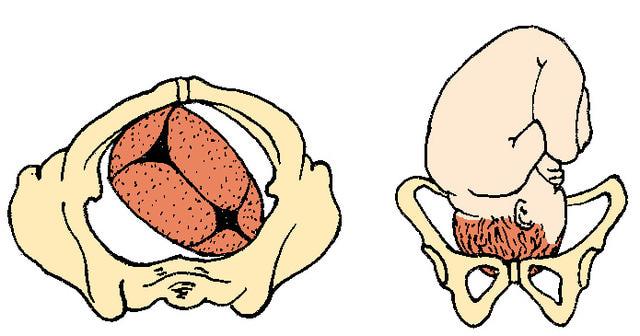

Complete Breech

Frank Breech

Footling Breech

What are the two footling breech positions?

single footling

double footling

How many babies are breech at term?

3% to 4%